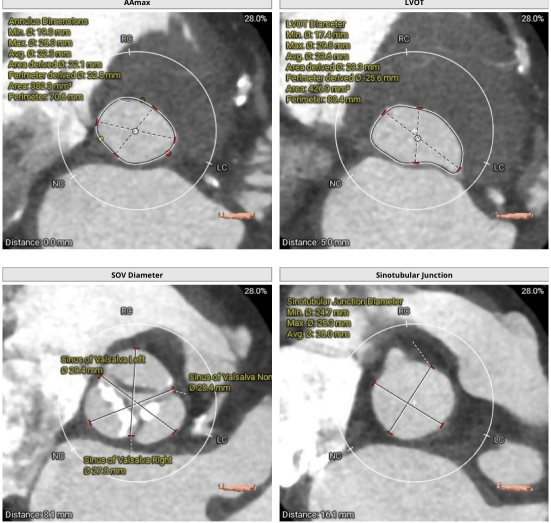

术前CT评估

图片

心超提示主动脉瓣重度狭窄伴轻中度关闭不全,二尖瓣轻度反流,左室壁肥厚,左心功能不全。

采用镇静加局麻的方式,经由右侧股动脉置入20F大鞘,20mm球囊扩张前测跨瓣压差80mmHg,选用MuguetA™ 23mm瓣膜,标准体积+1cc充盈,180bpm快速起搏下精准释放,手术位置理想(90/10%),主动脉根部造影提示微量瓣周漏,压差完全消失,冠脉开口通畅,心电图提示传导系统无影响,复查造影右股动脉未见明显狭窄,无造影剂外渗无夹层,手术效果良好。